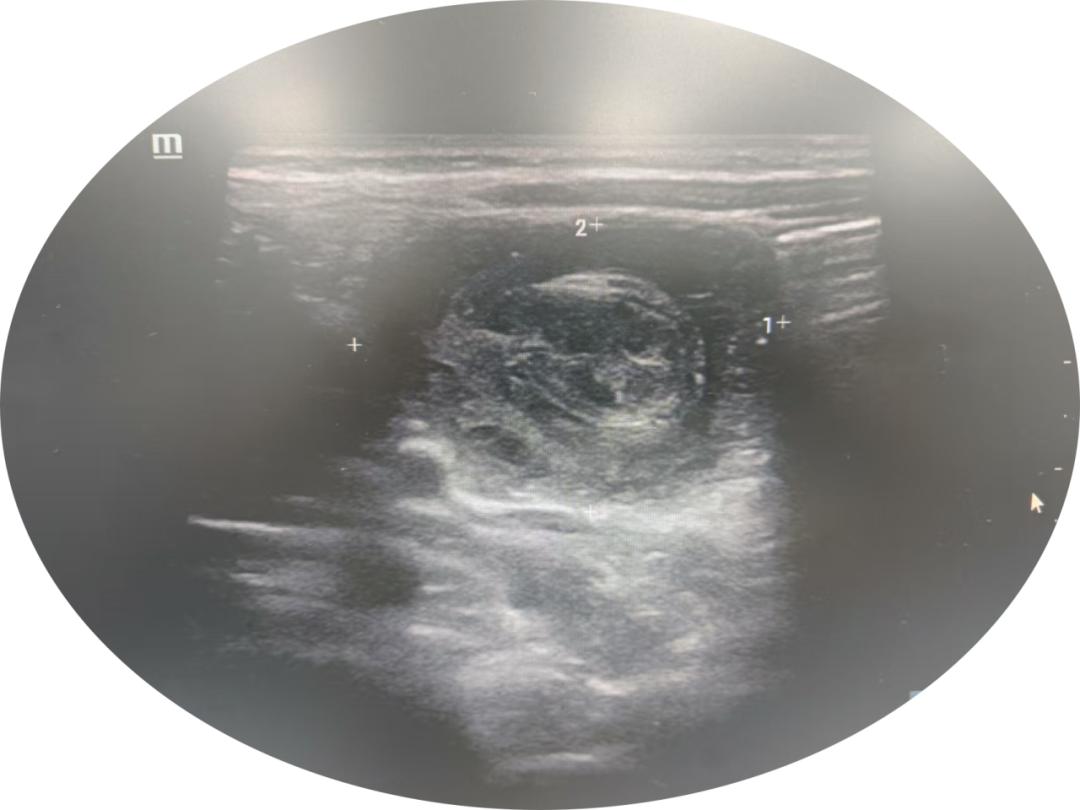

2025年7月10日下午,一位年仅2岁的宝宝,因为突发阵发性哭闹、频繁呕吐,被焦急的父母送到了广州中医药大学东莞医院(东莞市中医院)就诊。经过详细的超声检查,宝宝被确诊为“急性肠套叠”。

肠套叠,简单来说,就是一段肠管“钻”进了另一段肠管里面,就像把袜子卷起来一样。这种情况在2岁以下的宝宝中最为常见。肠套叠会导致肠道阻塞,引起剧烈腹痛、呕吐、便血(像果酱一样)等症状,有时甚至能在宝宝的肚子上摸到肿块。

这项技术就好比给医生安装了“透视眼”!在超声科医生的配合下,我们利用超声设备进行实时、动态的引导,通过肛门插入特制的导管,缓缓注入温热的生理盐水。

在超声屏幕上,医生可以清晰地观察到水流在肠道内的流动,精准地找到肠套叠的位置,并利用水压的轻柔、持续作用,将“套住”的肠管慢慢“解开”。

15分钟,宝宝重现笑容!整个过程仅用时15分钟左右!超声复查显示,肠套叠的征象完全消失,肠道的血液供应也恢复正常。宝宝的腹痛和哭闹迅速缓解,小脸上又露出了开心的笑容!